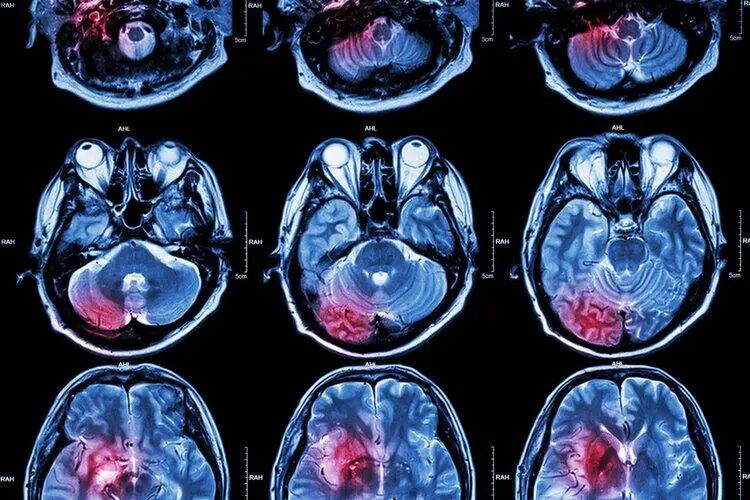

脑溢血,即脑出血,常被视为老年人疾病,然而,年轻人也面临着这一风险。探究其原因,需从生活方式和遗传等方面入手。

身体发出5个预警,则要警惕脑溢血

脑溢血常常伴随着一些先兆症状,如果及时警惕并采取行动,可能会避免悲剧的发生。以下是五个值得注意的预警信号: